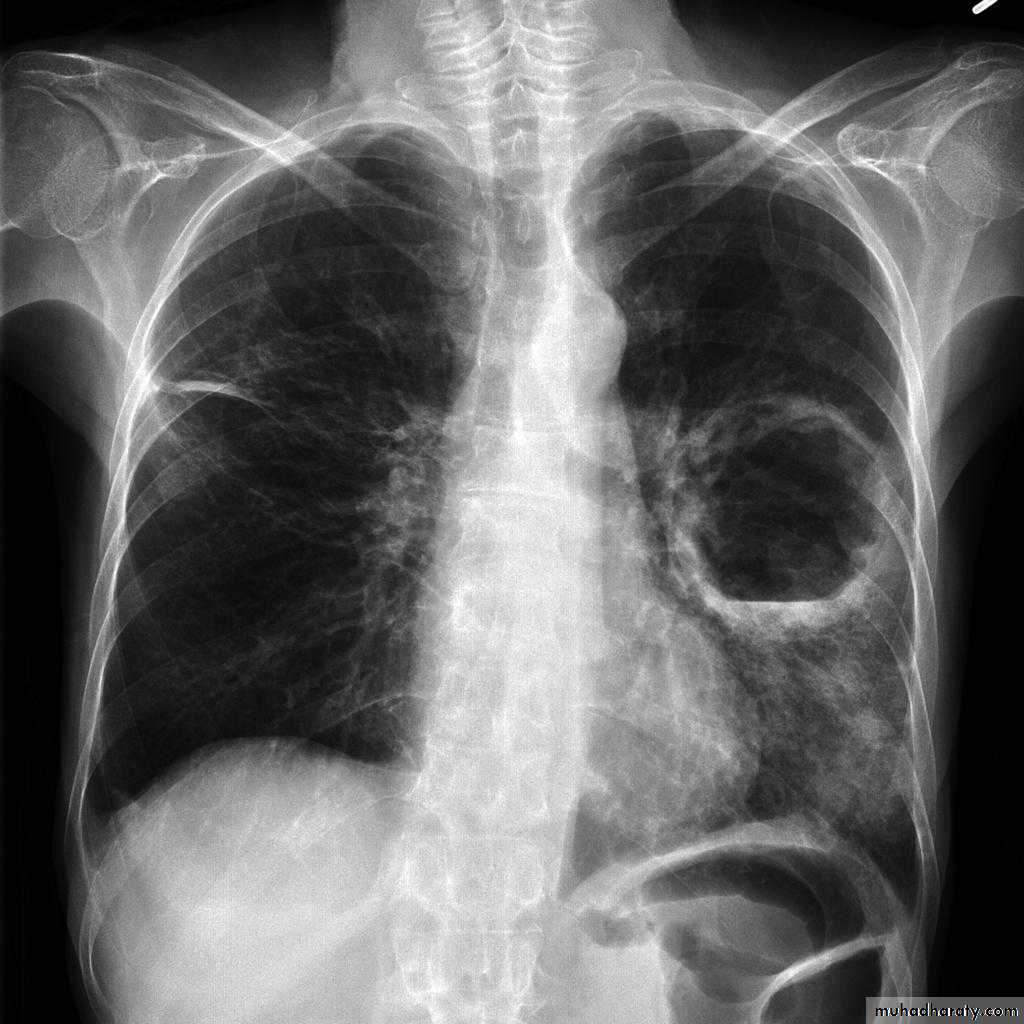

CXR : Air fluid level is only seen in upright filmCT san : clarify the diagnosis when the CXR is equivocal

1-CXR:

PA and lateral views show effusion, air fluid level

1-Cavitating lung carcinoma2- Infected lung cyst or bullae

3-TB

4- Bronchiectasis